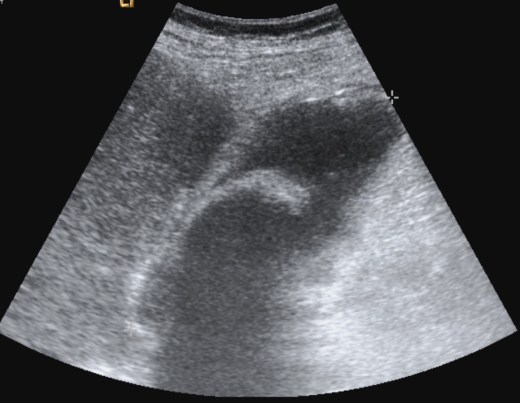

Se realiza ecografía abdominal:

Con estos hallazgos ecográficos podemos concluir que el paciente presenta una COLECISTITIS AGUDA.